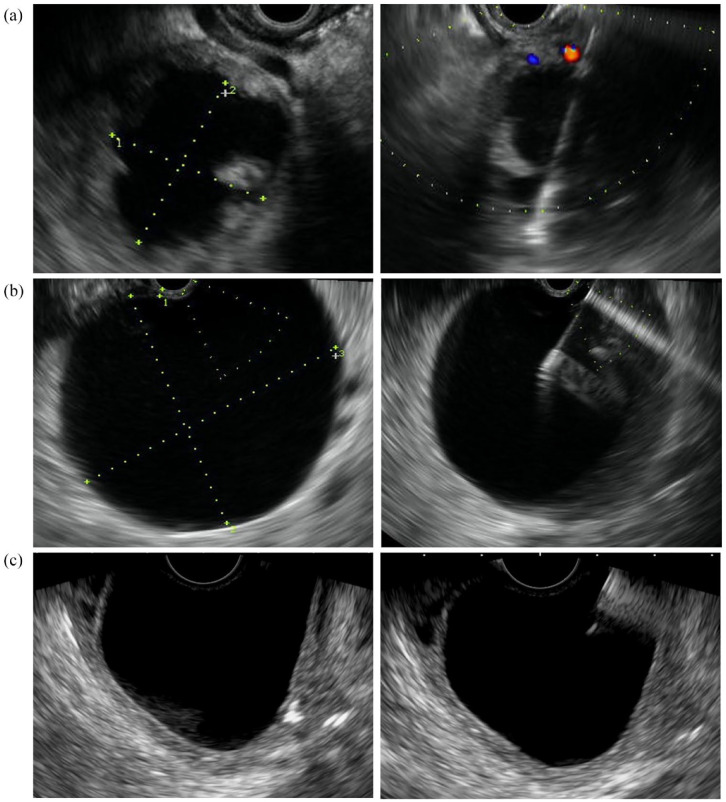

Graphical abstract:

背景:腹腔积液的内镜治疗包括内镜超声(EUS)引导下的经壁引流、经内镜逆行胰胆管造影(ERCP)的转胰管引流和 EUS 引导下的单纯穿刺抽吸(SPA)。后者鲜有报道,人们对其实际效用存在一些疑问:本研究旨在评估在 EUS 引导下将 SPA 作为一线方法治疗特定腹腔积液的有效性:方法:纳入所有连续腹腔积液患者:纳入2007年7月至2021年7月期间接受EUS引导SPA的所有连续腹腔积液患者。根据内镜医师的标准和腹腔积液的特征做出决定。临床成功的定义是避免了额外的介入方法(内镜支架、经皮引流、手术):结果:在 241 名经内镜治疗的腹腔积液患者中,有 55 人被纳入分析范围(平均年龄为 56 ± 12 岁)。积液特征:平均大小为 63.3 ± 24.8 毫米;22 例(40%)培养阳性,45 例(81.8%)为胰腺性质。所有病例均成功进行了 EUS-SPA,76.3%(95% 置信区间(CI),65.5-87.3)的病例(n-42/55)获得了临床成功。最常用的针头大小为 19 Ga(85%)。未感染的样本(84.8 vs 63.6;p = 0.07)和较小的样本(平均 ± SD;60.2 ± 22.9 vs 73.8 ± 29 mm;p = 0.09)的成功率呈非显著趋势。发现两例相关不良事件:一例出血,一例腹痛。五例假性囊肿在临床成功后发现复发。中位随访时间为 629 天(IQR 389-877):结论:对选定的腹腔积液进行 EUS-SPA 似乎是一种安全有效的技术,可避免采用更激进的策略(如经壁支架置入术)。EUS-SPA可能是规模有限且最好未感染的腹腔积液的可行替代方案:

Conclusion: EUS-SPA of selected abdominal collections seems to be a safe and effective technique, avoiding a more aggressive strategy such as transmural stenting. EUS-SPA may be a viable alternative in collections with limited size and preferably noninfected.